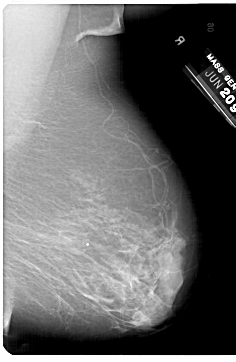

A_1329_1.RIGHT_MLO

RIGHT_CC LINES 6871 PIXELS_PER_LINE 4396 BITS_PER_PIXEL 12 RESOLUTION 43.5 NON_OVERLAY

RIGHT_MLO LINES 6871 PIXELS_PER_LINE 4471 BITS_PER_PIXEL 12 RESOLUTION 43.5 NON_OVERLAY